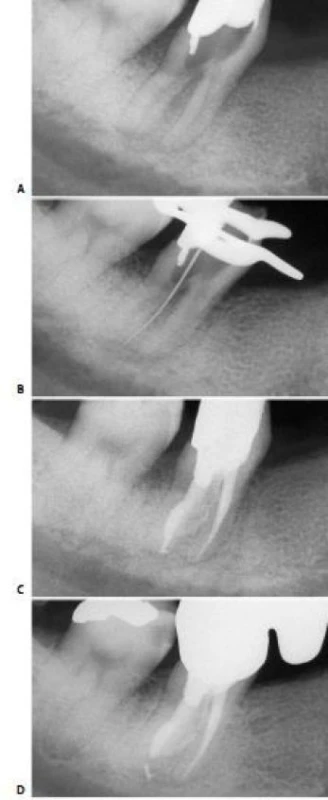

* Một ống tủy ở trong một chân xa, trong khi ở chân gần có hai ống tủy riêng biệt (hình 11.121) hoặc hai ống tủy gặp nhau tại một lỗ chóp (hình 11.122).

Hình 11.121. Răng cối lớn thứ hai hàm dưới với một ống tủy xa và hai ống tủy gần. A. Phim trước điều trị. B. Phim sau điều trị hai năm.

Hình 11.122. Một răng cối lớn thứ hai hàm dưới với một ống tủy xa và hai ống tủy gần giao nhau tại cùng một lỗ chóp. A. Phim trước điều trị. B. Phim sau điều trị.